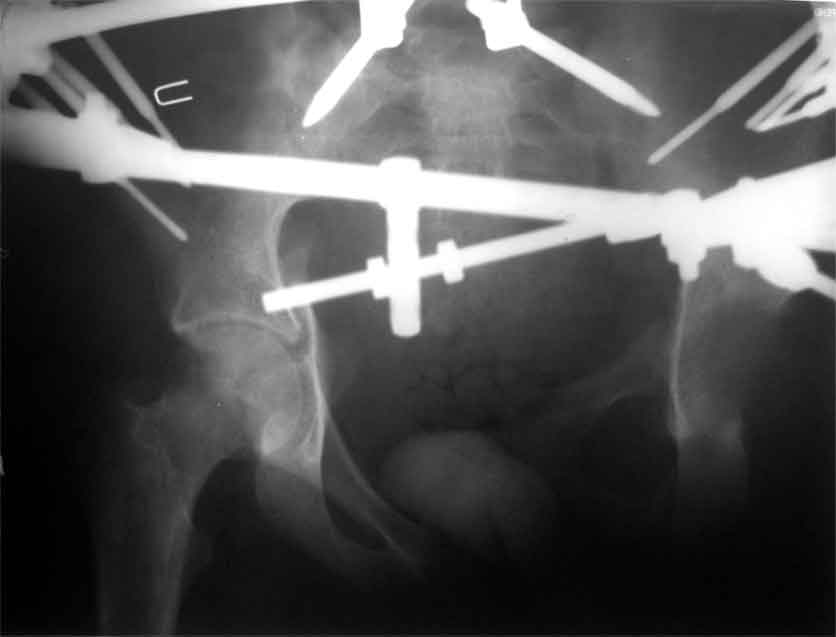

продолжение темы. не увидел энтузиазма в обсуждении. Вопросы прежние, первым этапом закрыто устранили вертикальное и передне-заднее смещение. Каким образом восстановить целостность тазового кольца, из каких доступов? Снимки в приложении